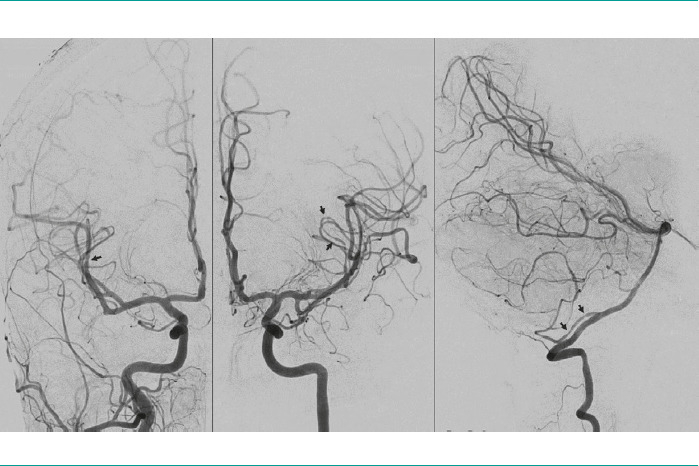

Case report: A 44-year-old woman with a history of multiple sclerosis treated with interferon beta-1b who had four episodes of thunderclap headache while resting, after completing a course of corticosteroids due to a flare-up of optic neuritis. Three years earlier, the patient had presented several episodes of explosive-onset headache during a self-limited period of one month, only occurring during sexual intercourse. In the year prior to our assessment, she had suffered three thunderclap headaches with similar characteristics, but they were triggered only by intense physical exercise. She had not consulted a physician about these events. A cranial computed tomography scan was performed after the administration of contrast media and a cerebral arteriography, which were consistent with cerebral vasoconstriction syndrome, and its reversibility was confirmed three months later.